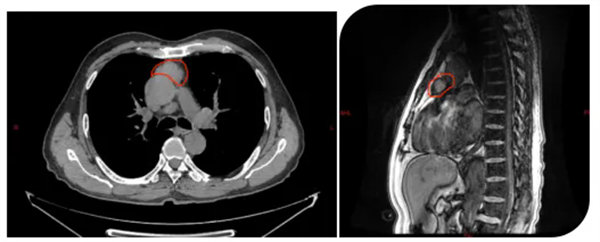

該患者體檢時(shí)胸部CT發(fā)現(xiàn)前上縱隔見團(tuán)塊狀高密度影,范圍約3.6cmX3.2cmX24cm,鄰近心包局部凹陷,考慮胸腺瘤。胸外腫瘤外科主任陳瑜率領(lǐng)團(tuán)隊(duì)仔細(xì)閱片并討論后確認(rèn)腫瘤與心包關(guān)系緊密,進(jìn)一步胸部磁共振檢查后明確心包存在侵犯,考慮侵襲胸腺瘤,手術(shù)指征明確。